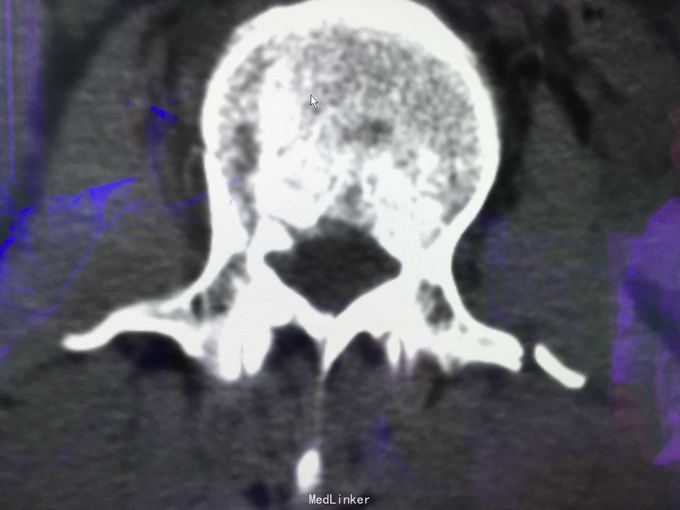

查体:左肾区叩痛,无皮肤隆起,未扪及肿块;腰椎压痛,活动受限,双下肢感觉存在,右小腿石膏托外固定,有踝关节明显肿胀,局部压痛活动受限,指端感觉血运可。 CT及X片:L2、L4椎体爆裂性骨折,L1-L4左侧横突骨折,右坐骨支骨折,右侧胫骨内、后及右侧腓骨外踝骨折,右足第1-4跖骨向外侧脱位及半脱位,伴近端斯脱性骨折。左肾挫裂伤,左肾重度积水,左肾周血肿。

诊断:右足lisfrance损伤,左肾挫裂伤;左肾周血肿,左侧输尿管结石伴左肾重度积水,L2、L4椎体骨折,L1-L4左侧横突骨折,右侧坐骨支骨折,右三踝骨折,全身多处皮肤软组织挫伤 处理:急诊行左肾探查,左肾切除术,择期行经后路腰2、4椎体骨折切开复位、椎公根螺钉内固定术+右内、外踝骨折切开复位内固定术,择期行右足lisfrance关节复位克氏针内固定术。